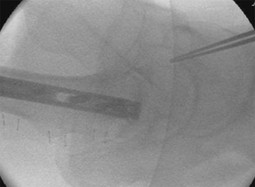

The surgical technique described in this article is the standard procedure for femoral shaft fractures and subtrochanteric fractures in this level 1 trauma center. The patient is positioned in a lateral position on a radiolucent table with free draping of the injured leg. Using the C-arm, reduction can be performed with this technique with precise placing of the nails and torsion can be exactly adjusted and controlled with the aid of the femoral neck axis, the distal locking holes and both parallel femoral condyles.